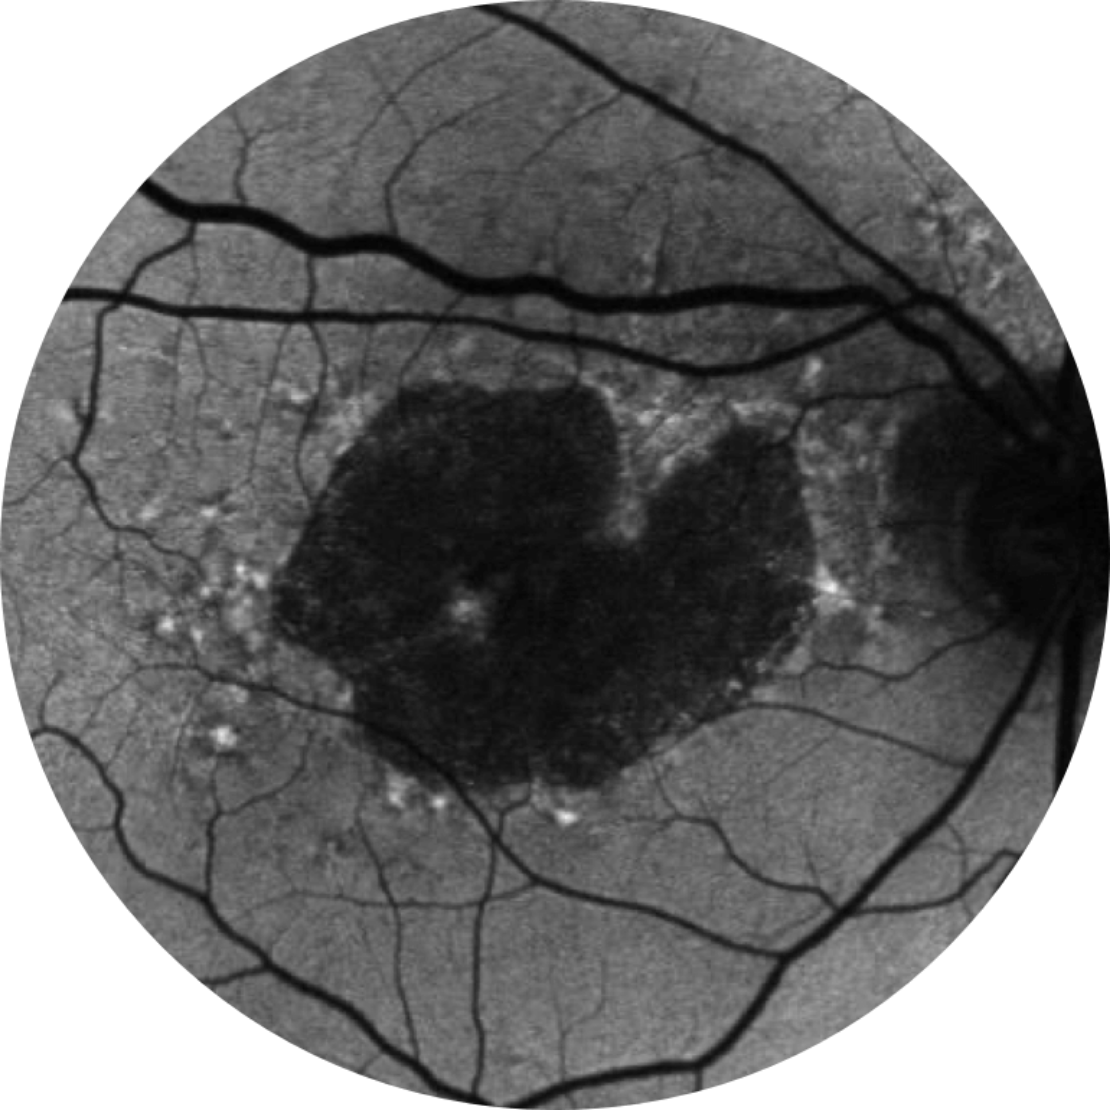

Normal fundus autofluorescence of a retina

Fundus autofluorescence angiography imaging is currently a standard imaging technology to visualise the retinal pigment epithelium (RPE) in geographic atrophy.20